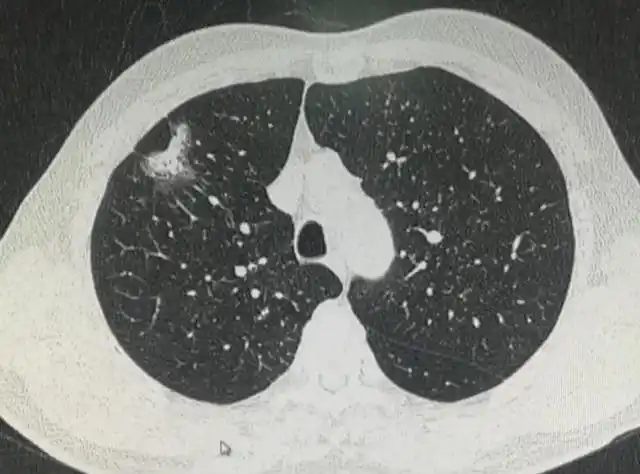

肺结节_良性肺结节的六个特征-第2张图片-体检知音

查出肺结节,怎么确定是不是恶性结节?